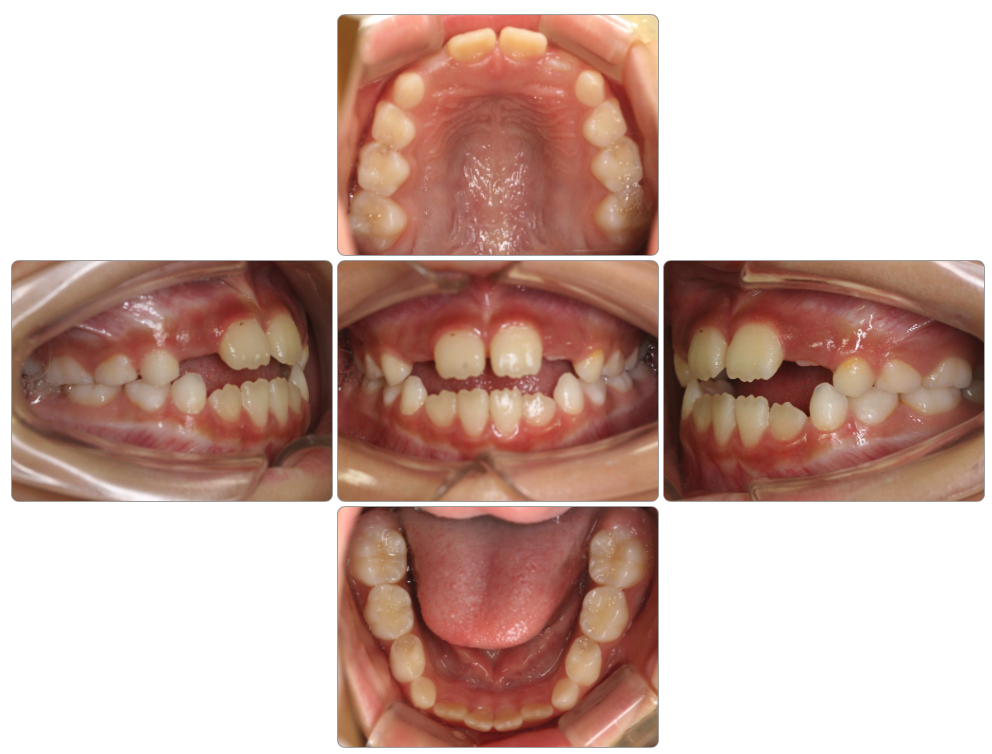

反対咬合の治療例

Before

after

| 初診時 | 6歳0ヵ月 |

| 治療期間 | 3年経過 通院中 |

| 費用 | ¥550,000・調整料¥5,500/月 |

| 使用装置 | マイオブレイス・BBI |

| リスクと副作用 | |

| 原因と考察 | 反対咬合は骨格性のものとそうでないものがあります。このお子さんは骨格性ではないのでマイオブレイスで改善しやすいと言えます。骨格性ではない反対咬合さんでは舌が口蓋をサポートしていないことで上顎部分が落ち込む(クロックワイズローテーション)ことで舌の前歯の後ろに上の前歯が入り込んで反対咬合になっている場合がほとんどですので、マイオブレイスを使用して舌が口蓋をサポートしてくると簡単に正常な状態に改善します。このお子さんの場合やや骨格も原因に入っているようですので後戻りには注意が必要ですが、基本的には姿勢・頭位を正しくすることで対応する必要があります。 |